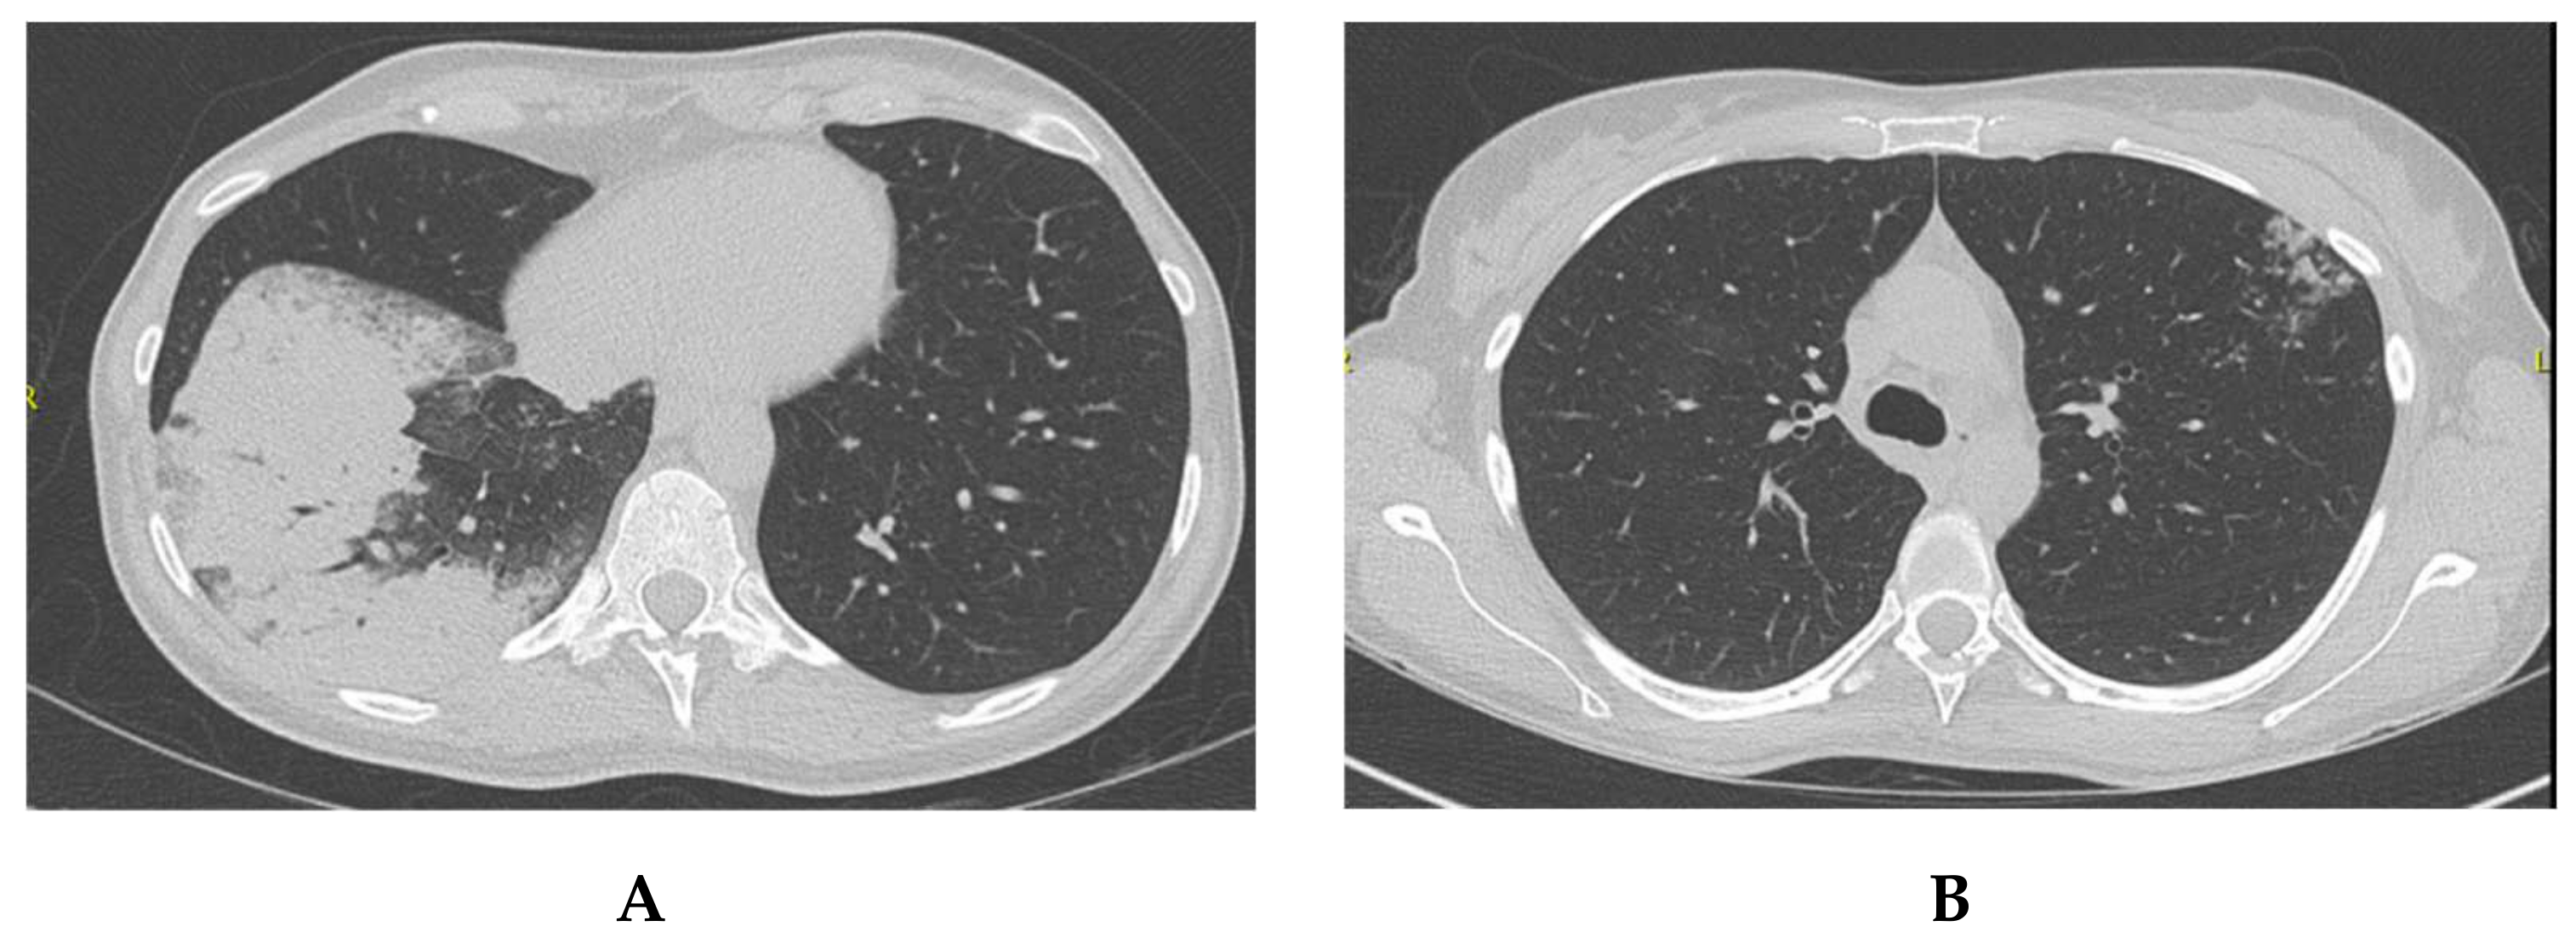

2.1. Patient 1